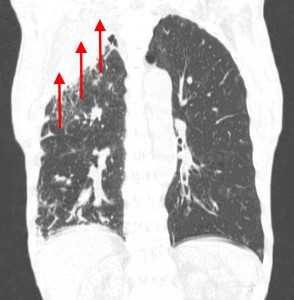

Гематогенные метастазы наиболее часто локализуются в периферических отделах легких, вдали от крупных сосудисто-бронхиальных пучков, вблизи плевральной оболочки. При множественных поражениях гематогенного характера наблюдается тенденция к увеличению количества очагов в направлении «сверху-вниз». Чаще гематогенные метастазы расположены хаотично, вне четкой связи с бронхами и видимыми легочными сосудами. Практически не бывает такого, чтобы гематогенные вторичные узлы находились только с одной стороны, или занимали только одну долю или сегмент. При наличии такого распределения в первую очередь нужно думать о туберкулезе (верхние доли), множественных абсцессах и т. д.

Гематогенные метастазы саркомы мягких тканей бедра на КТ (справа) и рентгенограмме (слева).